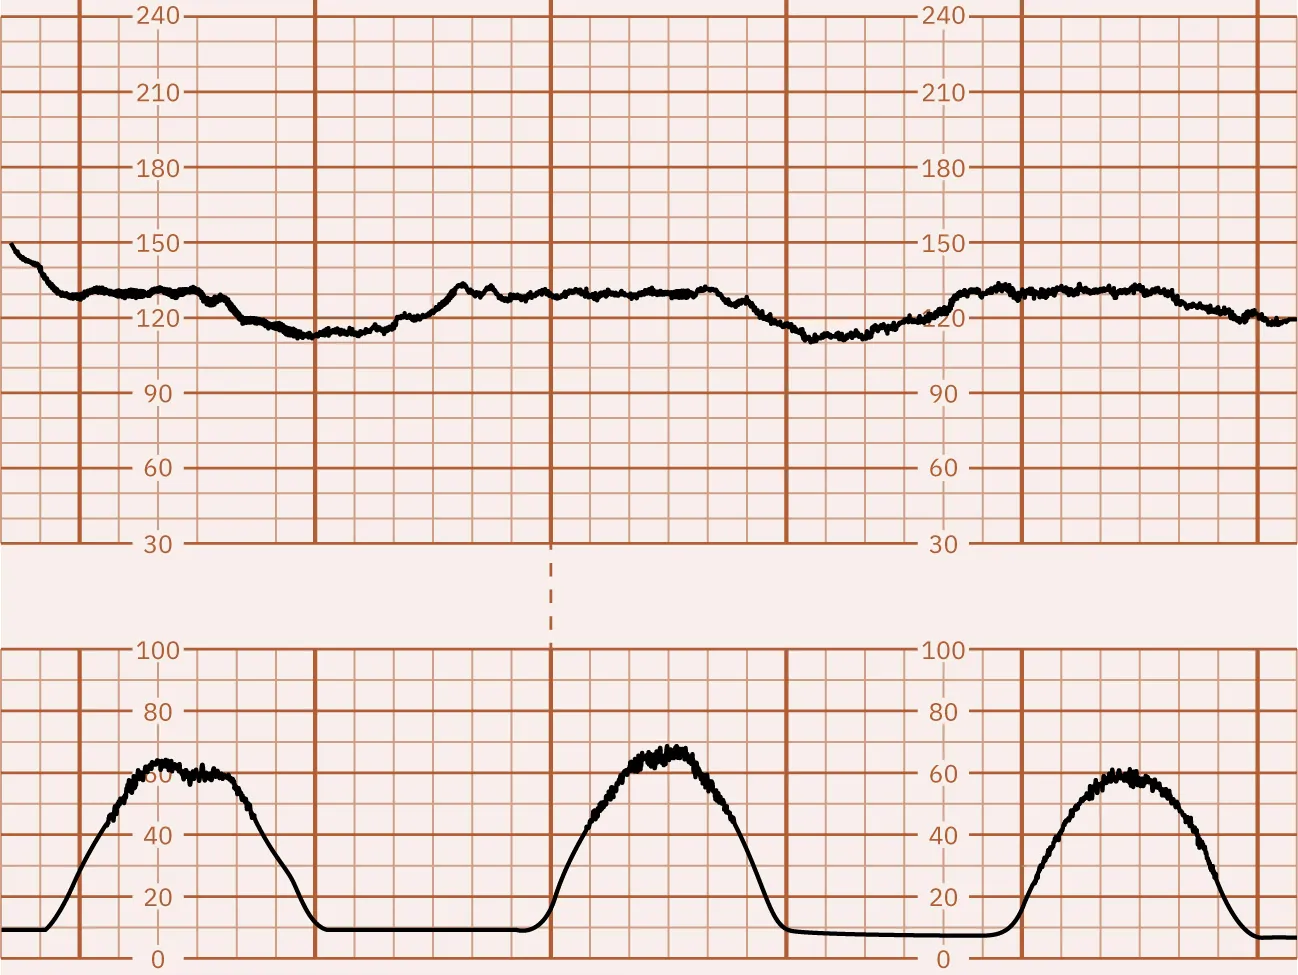

Describe the periodic changes in this monitor strip. Are they reassuring or nonreassuring?

Fetal heart rate reading showing periodic changes. The top graph shows a fetal heart rate ranging from 150 bpm, but it drops down to 110 bpm at periodic intervals. The bottom graph shows contractions that peak just prior to the FHR dips.